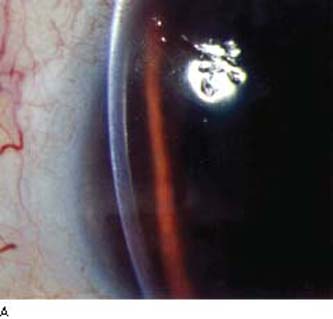

이러한 비정상적인 각막내피세포들은

각막 후면에서 희미한 회색의 소포(vesicle)이나 포진(blister)의 형태를 보이며,

선상이나 무리를 지어모여있습니다.

또한 깊은 각막 실질과 데스메막에서 증식하면서, band like thickening을 보여,

전형적인 tram track 양상을 보입니다.